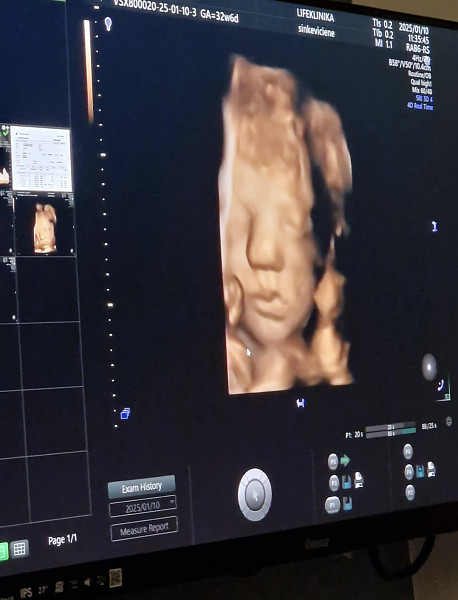

Jei neklystu 3D nufilmuoja kaip reelsą kokį ir tada parodo per ekraną, o 4D rodo realiu laiku, gali pamatyt kaip išraiška pasikeičia ir pan. Nu va man daryta praeitą penktadienį. Tai juokingai ta nosis tokia prispausta didelė atrodo, kaip Nida sako nelabai jau gražiai gaunasi 😂